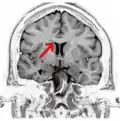

Corpus callosum from above, front part at the top of the image

The corpus callosum (Latin for "tough body"), also callosal commissure, is a wide, thick nerve tract, consisting of a flat bundle of commissural fibers, beneath the cerebral cortex in the brain. The corpus callosum is only found in placental mammals.[1] It spans part of the longitudinal fissure, connecting the left and right cerebral hemispheres, enabling communication between them. It is the largest white matter structure in the human brain, about 10 cm (3.9 in) in length and consisting of 200–300 million axonal projections.[2][3]